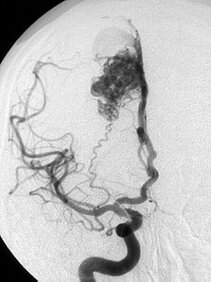

Bei einer Arteriovenösen Malformation, auch Angiom genannt, fehlt dieser Sauerstoffaustausch, das Blut fließt durch eine Kurzschlussverbindung (Nidus). Dieser stellt sich in der Bildgebung als ein Gefäßkonglomerat dar.

Angiographische Darstellung eines Angioms in 3D-Darstellung.